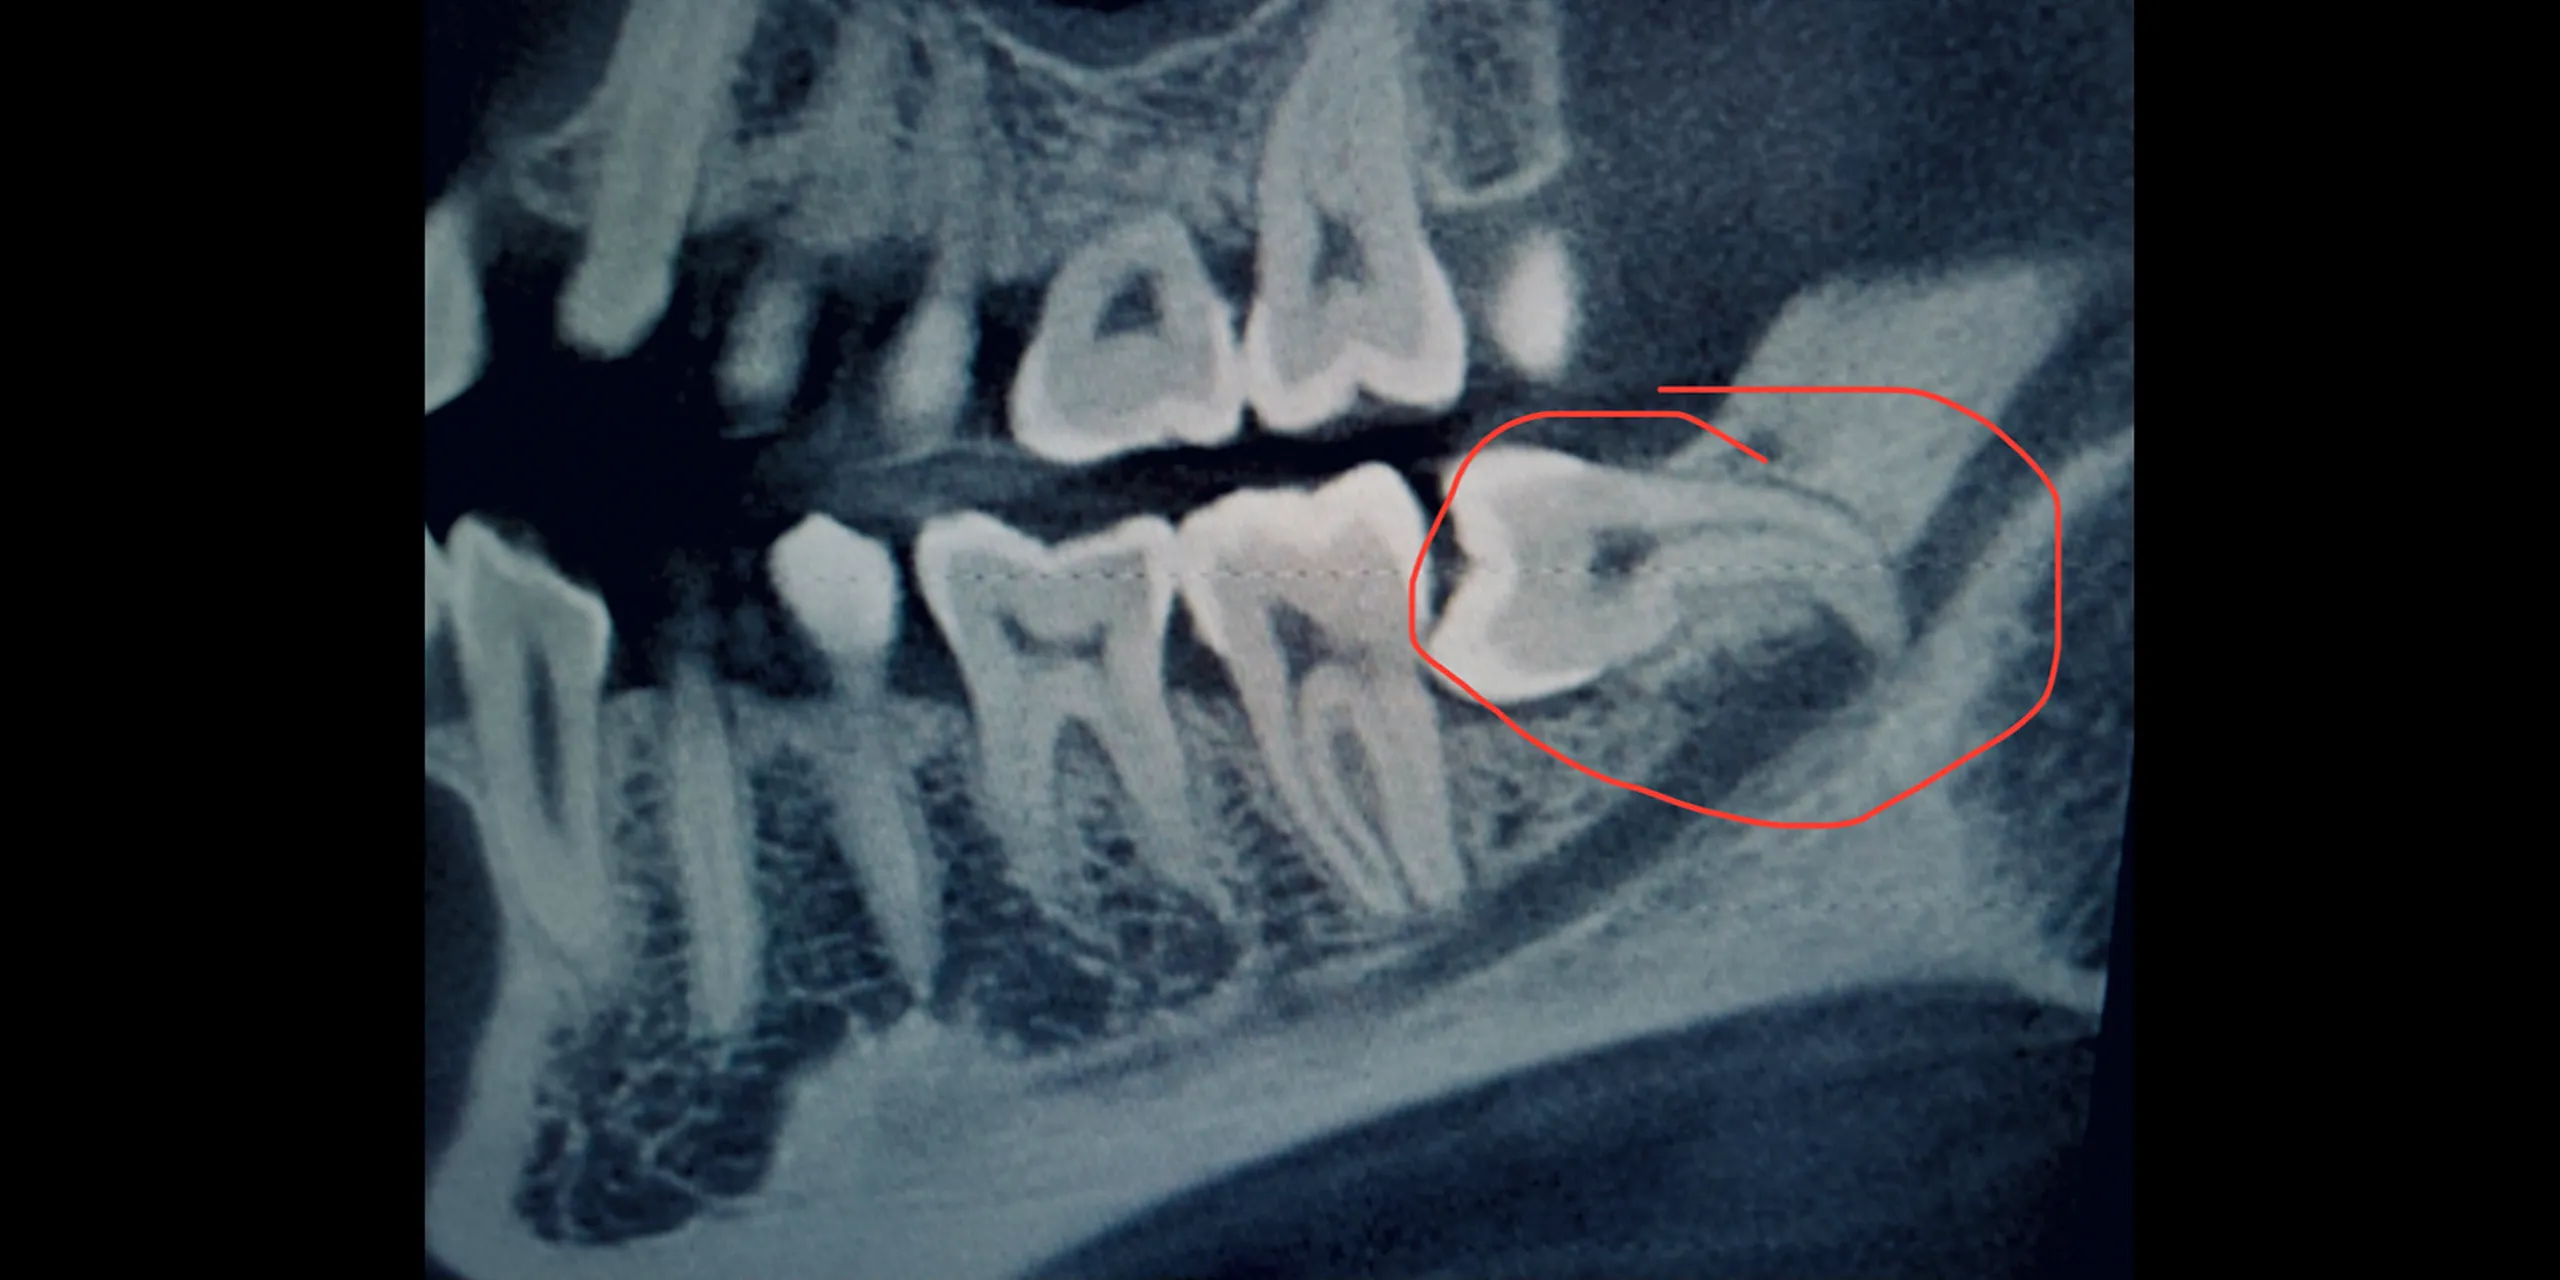

Tooth extraction is a common dental procedure, usually performed when a tooth is damaged beyond repair, infected, or causing crowding. Thai dental clinics generally provide two main types of extraction: simple extraction and surgical extraction.

1. **Simple extraction** – Suitable for teeth that are visible in the mouth. The dentist uses local anesthesia and special instruments to loosen and remove the tooth.

2. **Surgical extraction** – Necessary when the tooth is broken, impacted, or not easily accessible. This may involve making a small incision in the gum and possibly removing bone around the tooth.

You’ll find that most clinics use digital X-rays, 3D imaging, and computer-assisted technology to ensure precision. Sterilization processes meet global healthcare standards, and materials used for anesthesia or surgical care are imported from trusted sources.